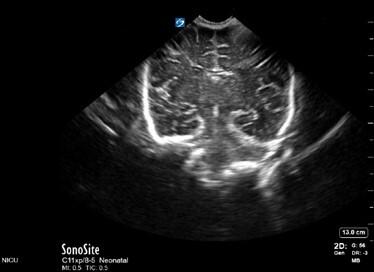

Neonatology Normal Anatomy Depth Too High Image